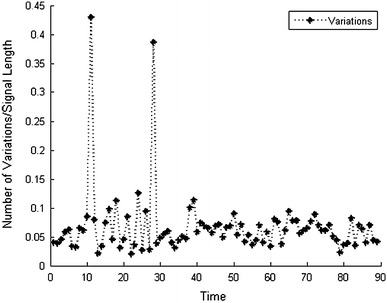

The key assumption of our work is that the variations of functional MR images are sparse over time in the wavelet domain. We demonstrate it for a fMRI sequence [15] in Fig. 1. In order to reduce the impact of measurement noise, the variations are filtered by a threshold which is determined by one-tenth the maximum variation in a given time interval. The sparsity level is determined by , where Nt refers to the number of two-level Daubechies-4 2D discrete wavelet transform (DWT) of the functional MR image at time t, and refers to the number of DWT coefficient changes with respect to the previous frame. In most cases, the number of variations is less than 10 % of the signal size. Note that the two outliers result from the high degree of similarity between the two time-adjacent images. When the two images are nearly the same, the maximum variation is so small that the noise impact is increased.

Fig. 1.

Example of sparse variations